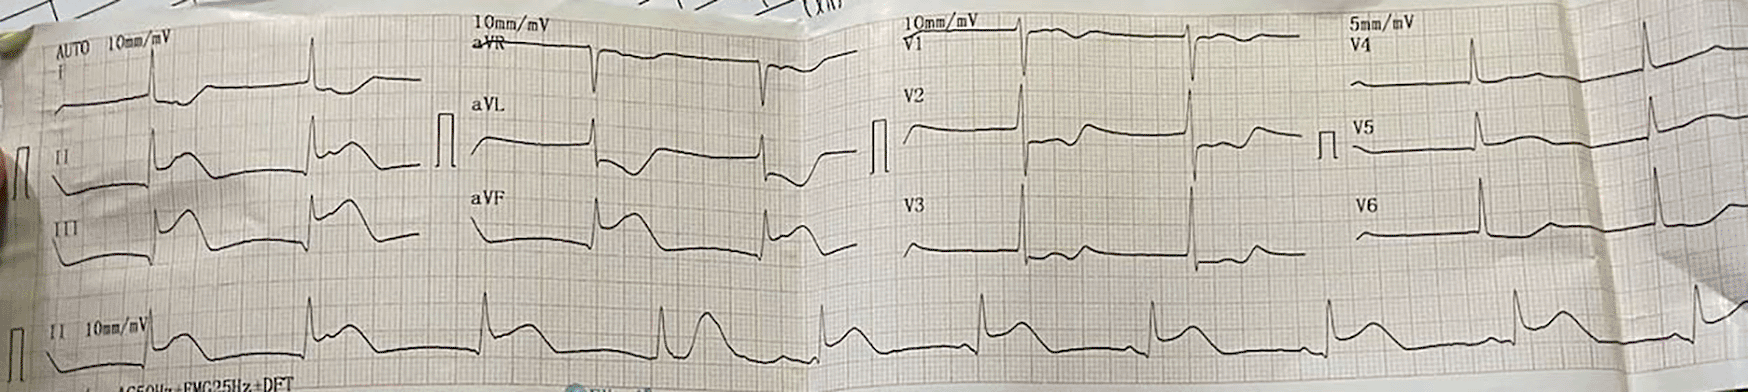

The electrocardiogram (ECG) of the patient showed TAVB with a junctional escape rhythm of 46 times per minute and inferior STEMI (Figure 1). The laboratory results of the initial visit were within normal limits, except that the blood urea nitrogen (BUN) 138 mg/dL (normal range: 8 – 23 mg/dL), creatinine serum 8.1 mg/dL (normal range: 0.6 – 1.3 mg/dL), haemoglobin (Hb) 8.6 g/dl (normal range: 11.5 – 16.5 g/dl) and troponin I increased to 30.6 ng/mL (normal range: ≤ 0.04 ng/mL).

We attached the ECG result during inferior STEMI with TAVB in this patient (Figure 1). We also attached the picture of coronary angiography that clearly show total occlusion of right coronary artery (Figure 2a). We also included the management of TAVB in ACS in the discussion.